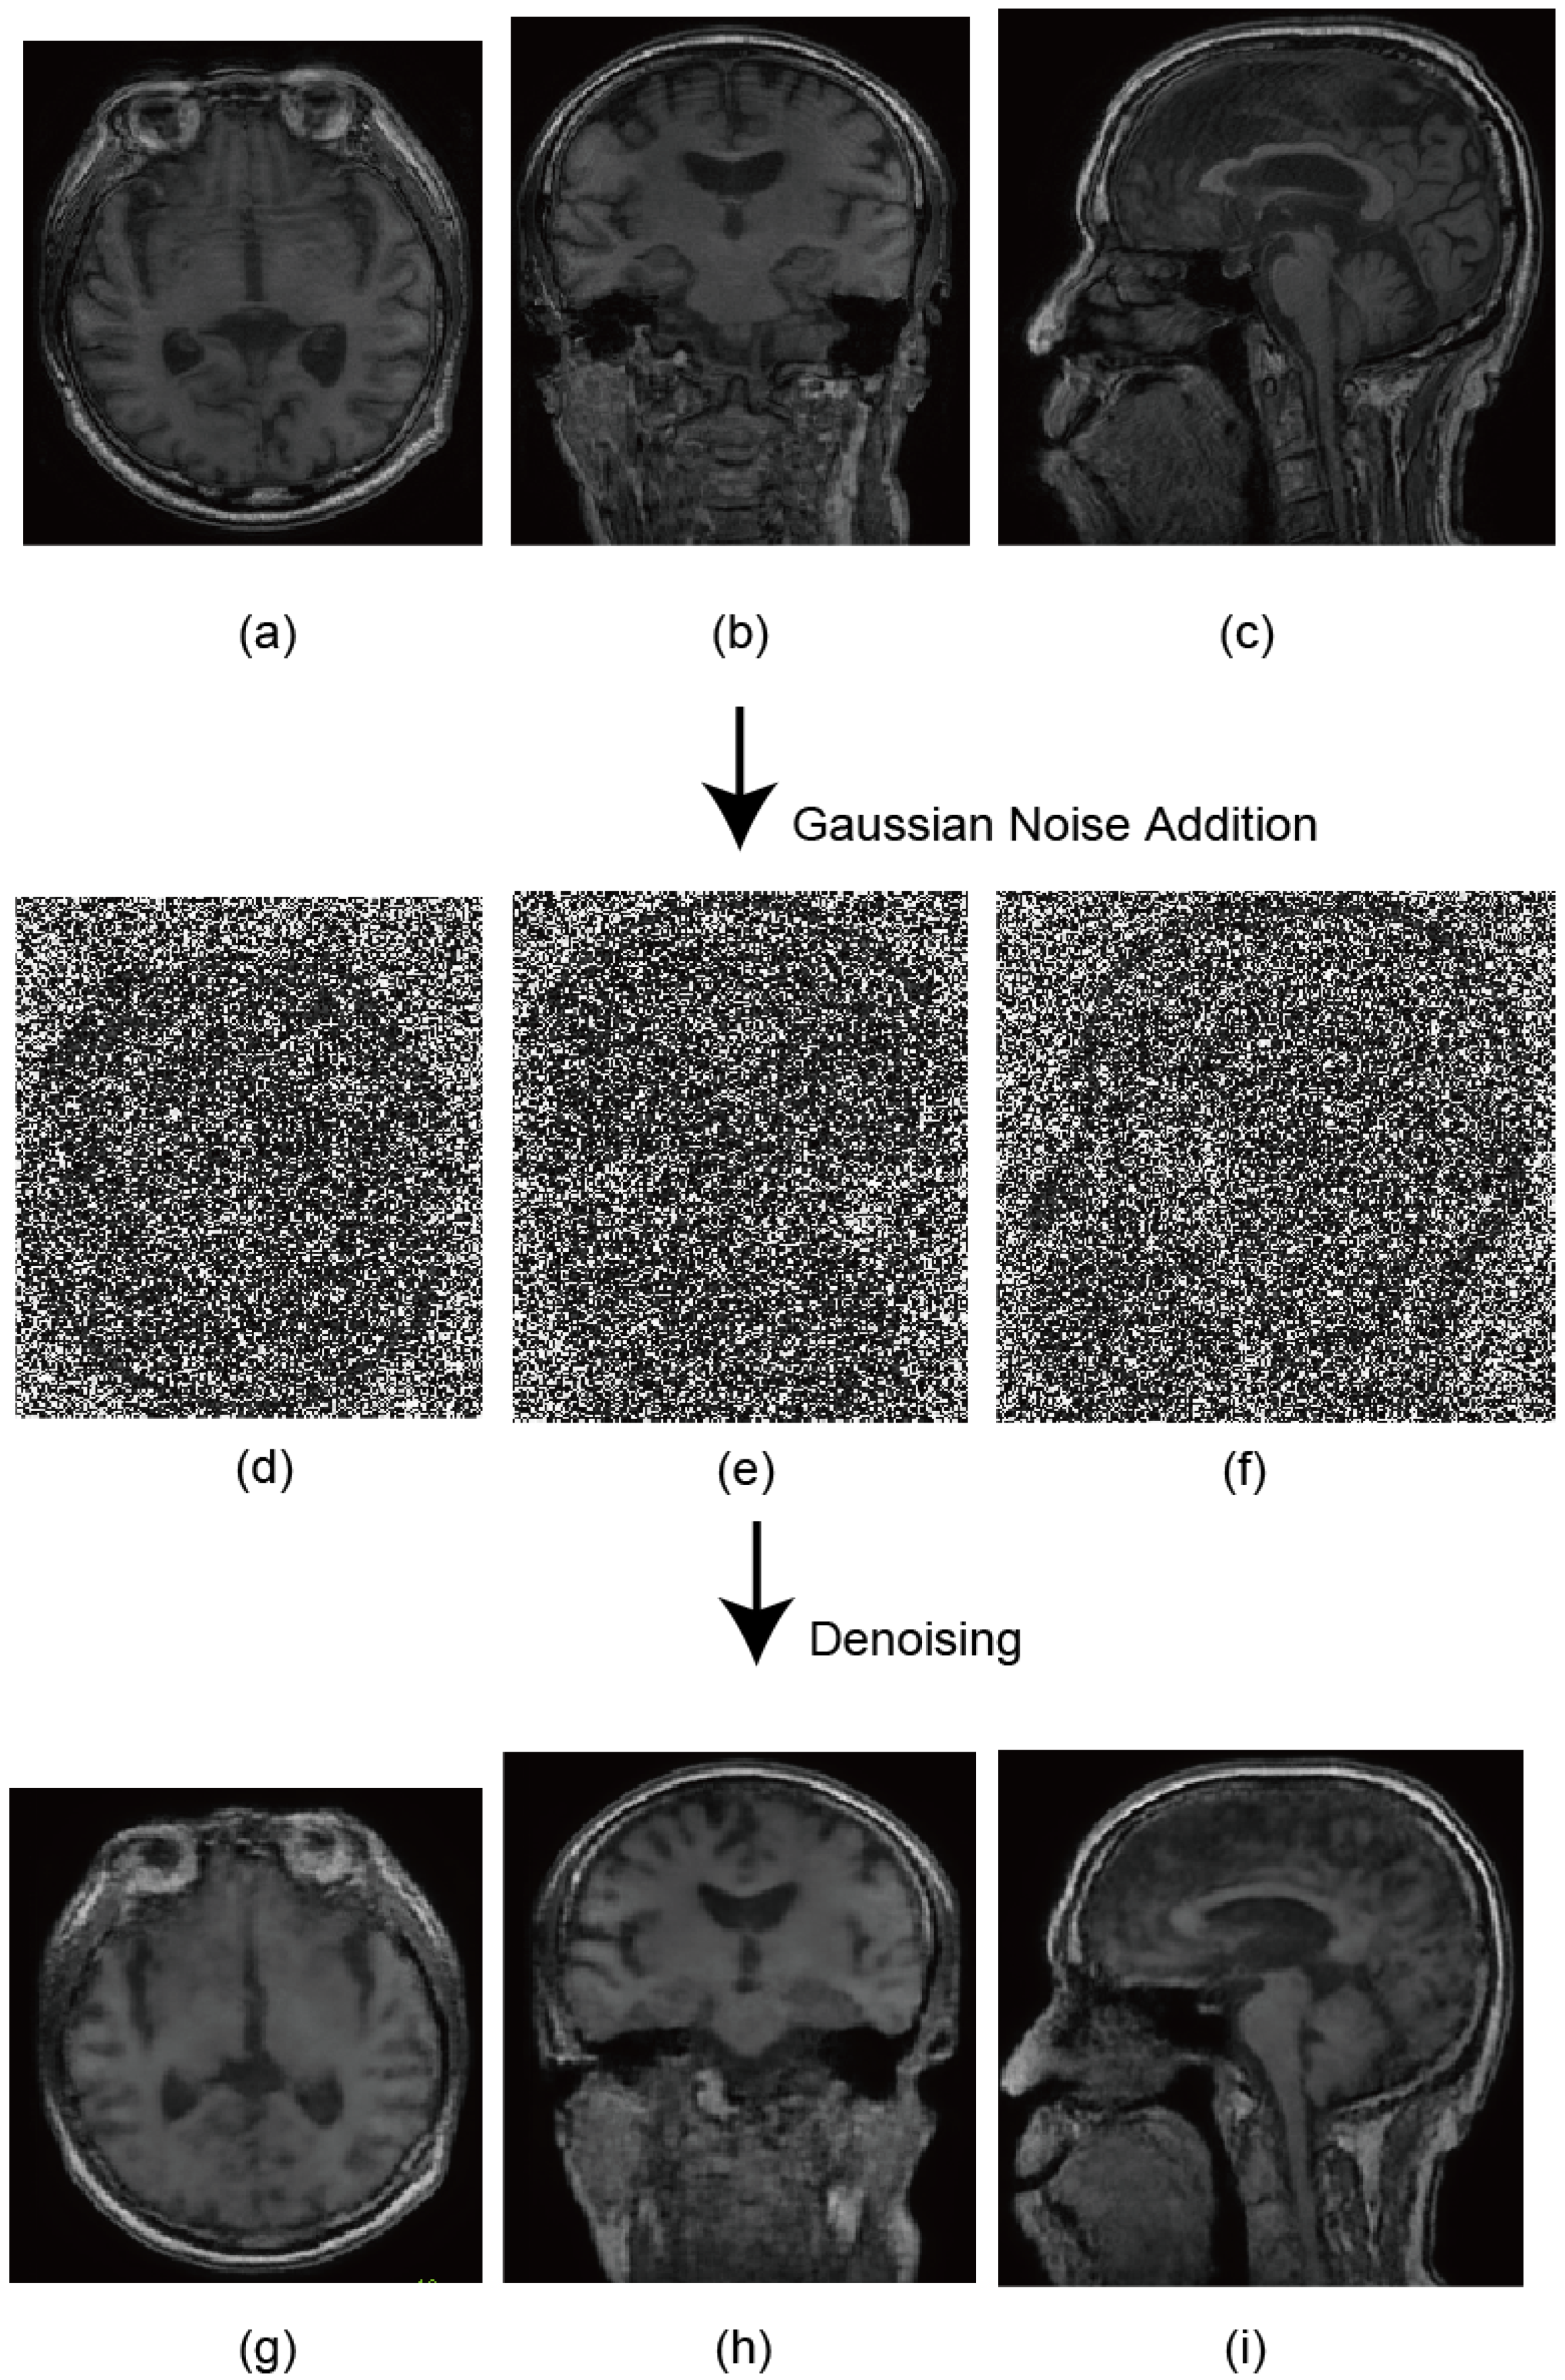

4.1. Preparation of Head MR Images

5.1. Unconditional Image Generation and Visual Evaluation